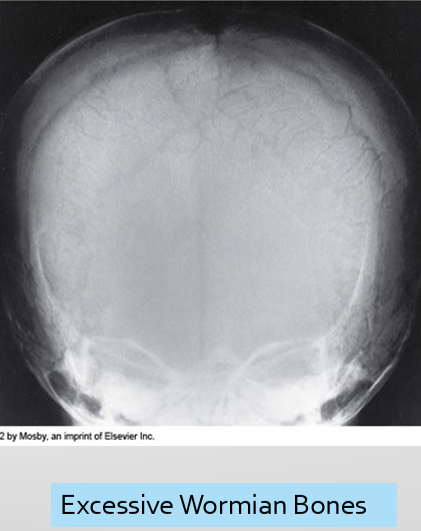

Radiographic Appearance - Osteogenesis Imperfecta

osteoporotic bones, thin cortices

callus formation

widened sutures, multiple wormian bone

Treatment - Osteogenesis Imperfecta

focus is to prevent fx → extendable rods in long bones